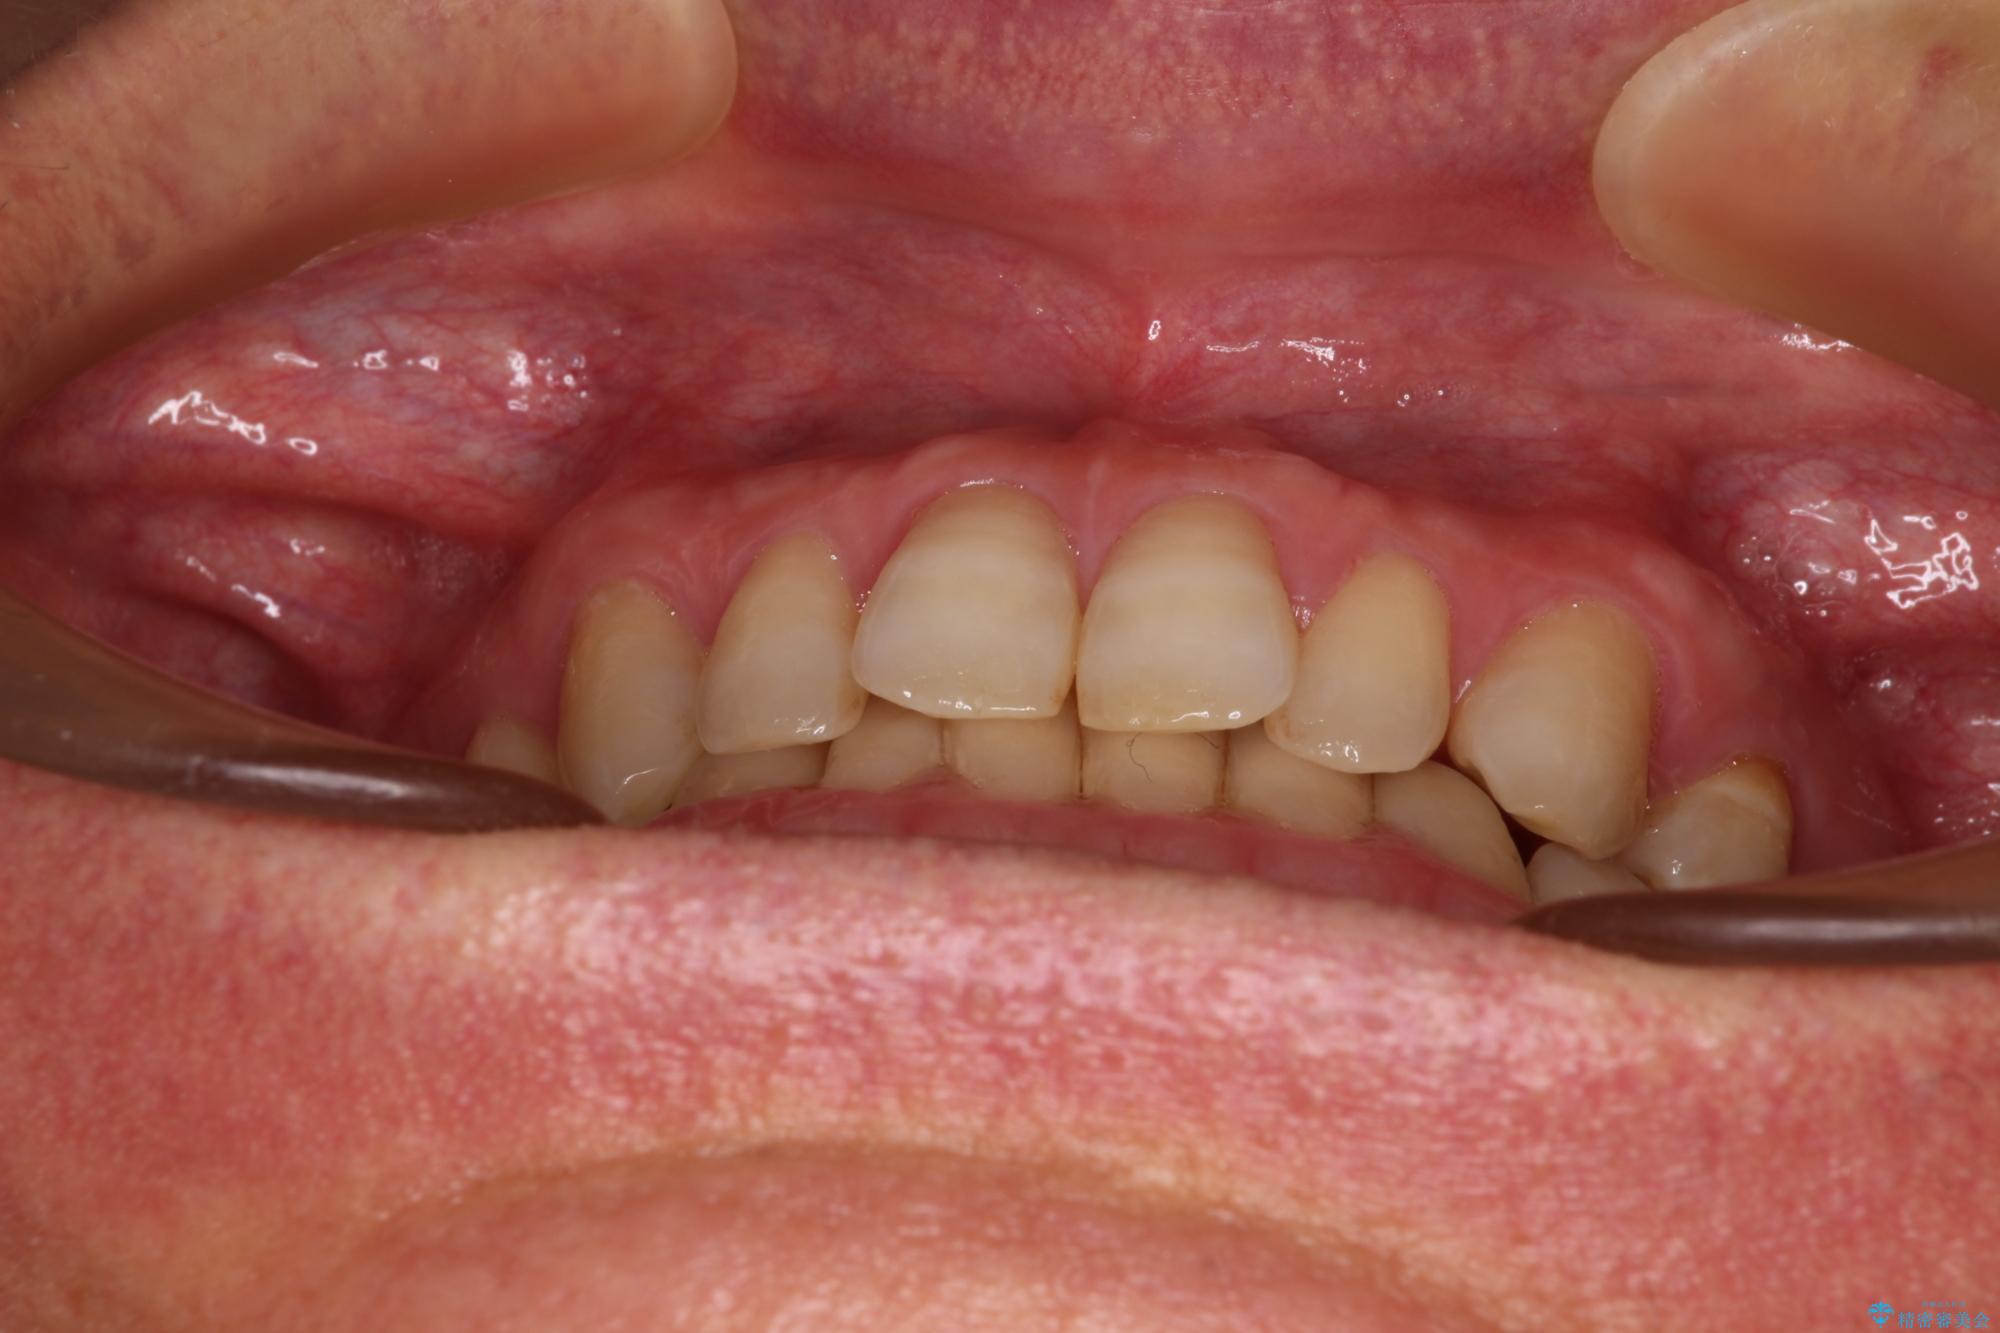

【モニター】ディープバイトで隙間の空いた歯列 ワイヤー装置での非抜歯矯正

- 前歯のデコボコと隙間の空いた歯列を気にして来院された患者様です。

下顎前歯が隠れるほどのディープバイトにより、強い咬合力と突き上げで上顎歯列に隙間が空いている状態でした。

ディープバイトが改善され、睡眠時の食いしばりも緩和され、顎への負担が軽減されました。